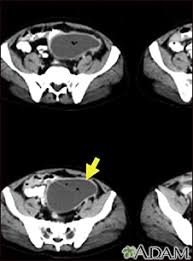

Abscesos Intraabdominales Trastornos Gastrointestinales Manual Msd Version Para Profesionales